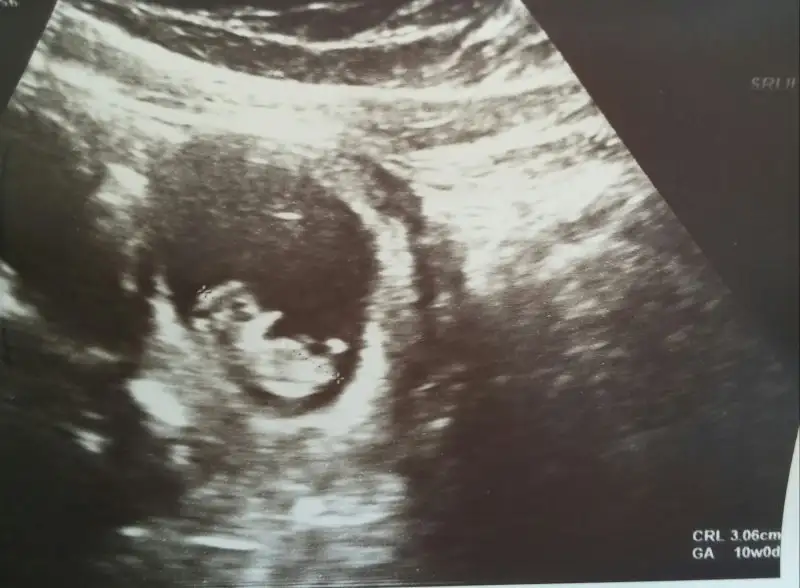

Kizlar doktordan ciktik cok şükür gayet iyi dedi masallah 6 kat büyümüş 3 haftada :KK46:@feministic canim sana da haber verecektim aklimdaydin.resmimizede bakin darisi bekleyenlere insallah

Maşaallah Can'ım. Çok sevindim; artık Bebek görüntüsünü almış gerçekten maşaallah. Bana da moral oldun ;)

Maşaallah Can'ım. Çok sevindim; artık Bebek görüntüsünü almış gerçekten maşaallah. Bana da moral oldun :KK66:

Canım sen nasılsın nasıl gidiyor. Ne zama gideceksin dr à. Aynı günüz seninle. Bugün 10 hafta yaşını doldurdu bizimkiler. Nice yaşlara inşallah :)))